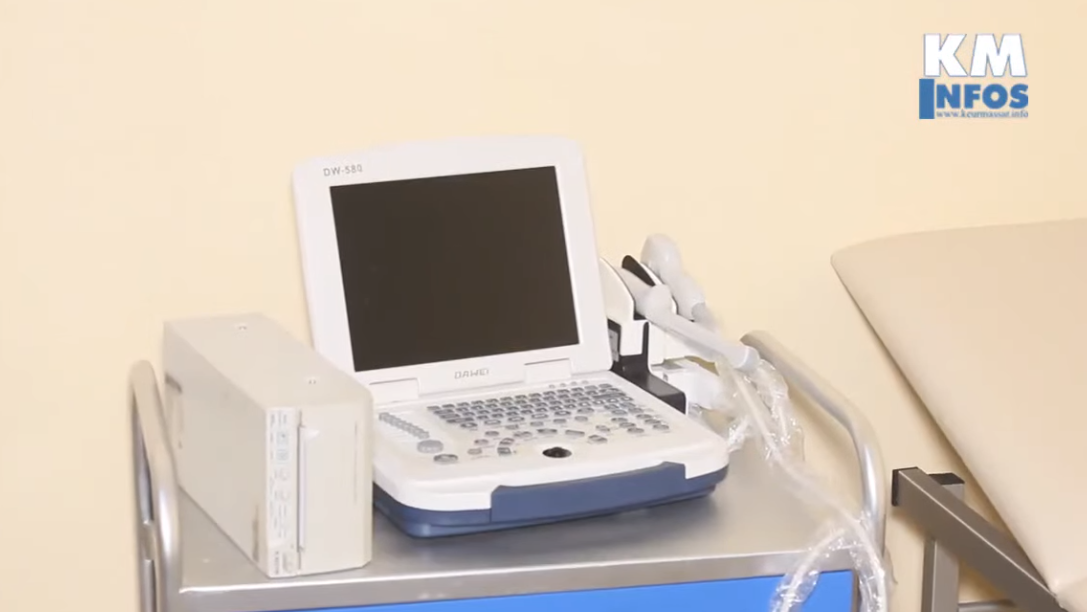

MEDIC'AOS est un plateau médical situé à Keur Massar offrant différents services : médecine générale, gynécologie, obstétrique, soins à domicile, transport de malades.

MEDIC'AOS fait intervenir de nombreux généralistes et spécialistes mettant leur savoir et leurs compétences au service des patients pour une prise en charge médicale de qualité.